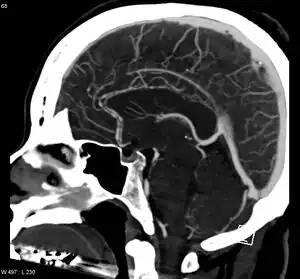

Significant beading of all intracranial arteries, best demonstrated in the anterior cerebral arties due to RCVS.